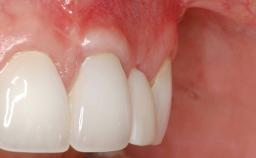

This case demonstrates that a connective-tissue graft in combination with a coronally positioned graft is an effective method of treating cases with peri-implant mucositis and an abutment-level sinus abscess. A 42-year-old man presented with a swelling adjacent to an implant crown at site 21. The swelling had been present for approximately three weeks and was constrained to the buccal and palatal gingival aspects of the implant. A discharge was noted on finger pressure, with localized gingival recession present on the mid- and distolabial aspects of the crown.